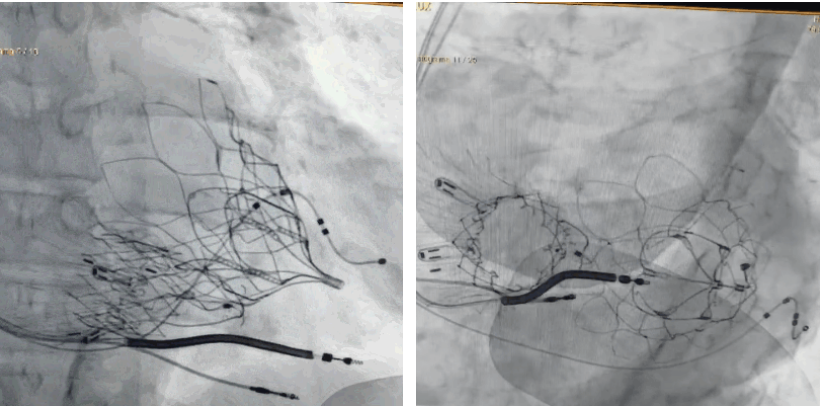

術后DSA顯示Lux-Valve Plus與Tendyne和ICD無相互影響

手術在全麻狀態下進行。術者采用經右側頸靜脈入路的方式將輸送器送入患者心臟內,在TEE及DSA引導下調整輸送器頭端角度,使得輸送器與三尖瓣瓣環平面垂直。在輸送器進入右心室后釋放室間隔錨定裝置,而后釋放瓣葉夾持件(2個耳片結構)成垂直狀態。在TEE及DSA確定夾持件固定至三尖瓣葉根部且位于右室側后釋放人工瓣心房側盤片。隨后調整瓣膜同軸性以及室間隔錨定件位置(貼合室間隔),前推藏針管并固定,進而釋放室間隔錨定裝置,并再次確認瓣膜位置、穩定性及同軸性,合攏輸送鞘后撤出輸送器,完成LuX-Valve Plus人工三尖瓣瓣膜的植入,僅殘余微量瓣周漏。且經手術中心電生理團隊評估,病人的起搏器和ICD功能沒有受到影響。